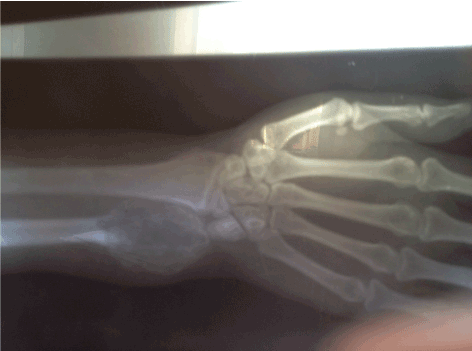

Figure 2. Lesion involving the distal ulnar.